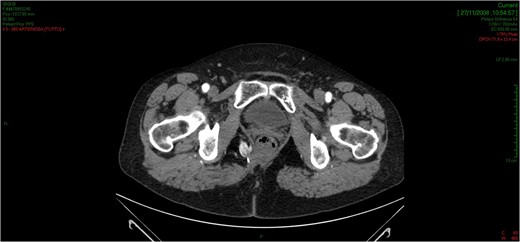

CT showed an hyperintense and inhomogeneous solid lesion taking up the right ischiorectal fossa (maximum diameter of about 10 cm), extended cranially until impressing the wall of the rectal ampulla, with no apparent infiltration (Figs 2 and 3). The lesion presented an intense contrast enhancement, sign of a rich vascularization (Fig. 4).

The CT scan demonstrates a solid neoformation in the right ischiorectal fossa.

The lesion extends cranially until impressing the wall of the rectal ampulla, with no apparent infiltration.